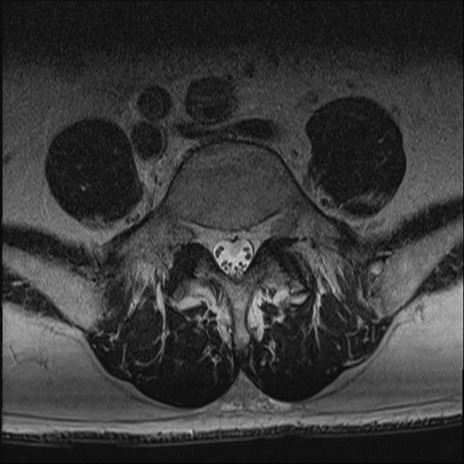

【整形】TIPS症例2 腰椎MRI T2WI(横断像)

【症例】70歳代男性

【主訴】左下肢痛

【現病歴】2週間前くらいから腰痛、左下肢痛あり。左臀部から大腿、下腿外側のしびれが常時ある。歩行とともに同部位の痛みあり。

【身体所見】Lasegue70-/60+、Bragard-/±、PTR ±/±、ATR -/-、IP 5/5、TA 5/4、TS 5/5、EHL 右第1足趾なし/3、FHL 5/5、hypersthesia(-)、足背動脈触知良好

異常所見と診断は?